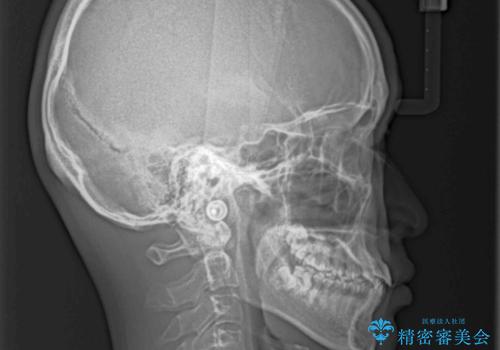

前歯のクロスバイト インビザラインによる矯正治療

- 上下のクロスバイトと前歯のデコボコを気にして来院された患者様です。

インビザラインを用い、IPR(歯と歯の間を削る)と歯列全体を拡大させることで、歯並びを整えていくこととしました。

上下ともに歯列全体を後方に移動させるため、上下の親知らずを抜歯することとしました。